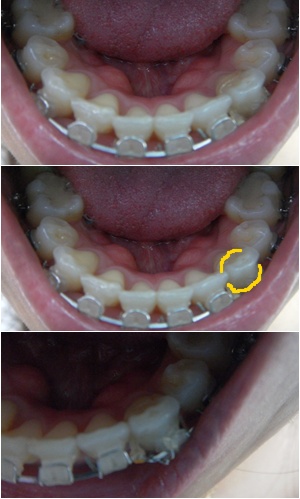

라인이 살짝 안 맞는 아래 앞니를 맞추기 위해 와이어를 구부리고 파워체인을 한바퀴 감아 당겨 주었어요~

그 결과~ 이렇게 전체적으로 U 라인이~ 짜자쟌~ ' ㅁ')b

두꺼운 와이어로 교체하고 파워체인 연결하고~

진료 끝나고 나서 다시 고무줄 걸기~

작은 고무줄을 이용해서 요렇게 삼각형 모양으로 거니까~

많이 땡기네요~ 그래도 부지런히 걸긔ㄱㄱ~ㅎㅎ